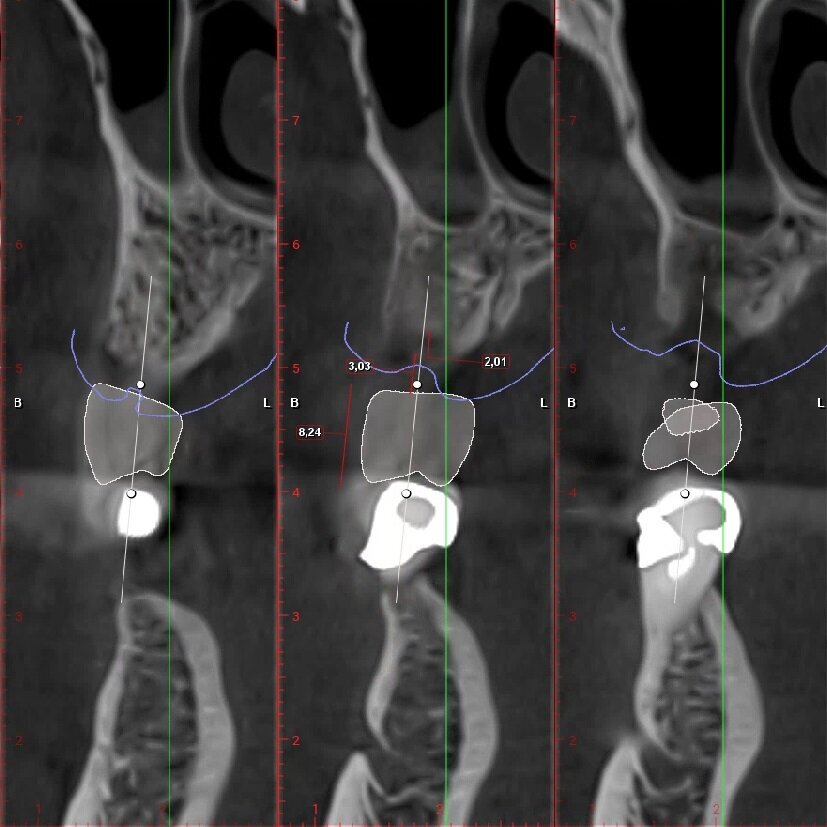

Fig. 4_Ceratura diagnostica elemento 2.5. Dimensione corono-apicale della corona congruente con elemento controlaterale 8,24 mm, tragitto trans-mucoso 3,03 mm, entità della rigenerazione ossea verticale necessaria 2,01 mm.

Fig. 5_Ceratura diagnostica elemento 2.6. Dimensione Corono-apicale della corona congruente con elemento controlaterale 8,00 mm, tragitto trans-mucoso 3,01 mm, entità della rigenerazione ossea verticale necessaria 2,81 mm.